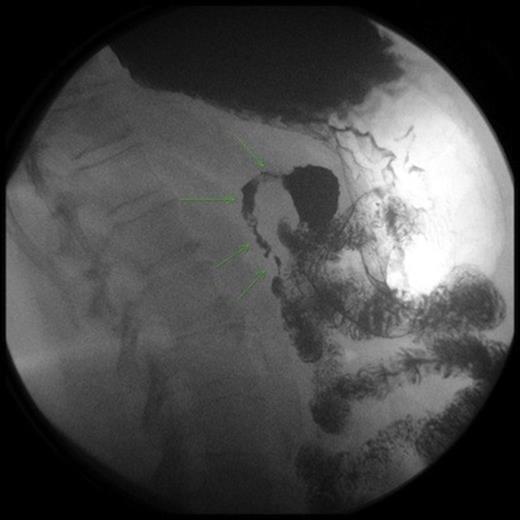

An upper endoscopy showed distal tertiary esophageal contractions, small sliding hiatal hernia with mild gastroesophageal reflux, and an intestinal obstruction at the level of the second portion of the duodenum. The mucosa was normal with the lumen completely constricted. A CT scan demonstrated distension of the stomach and first portion of the duodenum. An UGI study showed severe stenosis of the second portion of the duodenum.

An exploratory laparotomy demonstrated an olive type mass in the second portion of the duodenum involving a 5 cm segment of the second portion of the duodenum with thickening of the duodenal wall measuring up to 1.3 cm. A longitudinal duodenotomy showed a diverticulum at the ampulla and two biopsies of the wall were taken. The incision was closed longitudinally and a gastrojejunostomy was performed.